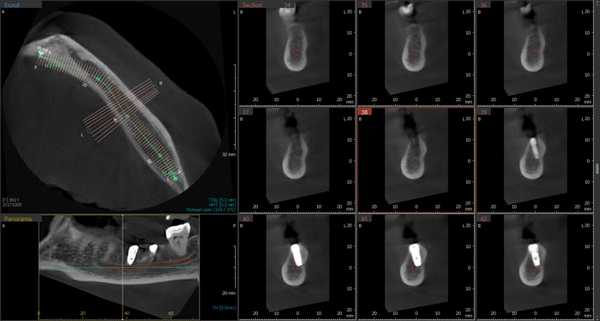

Рис. 1. Асимметричное строение нижнеальвеолярного нерва, добавочный канал в области нижней челюсти справа во фронтальной проекции конусно-лучевой компьютерной томографии от Vatech.

Лучевое обследование проводилось на различных этапах имплантации. Как правило, всем пациентам выполнялась ортопантомография на дооперационном этапе. В сложных клинических ситуациях использовались дентальная объемная томография. Изучение литературных источников по топографической анатомии лицевого скелета показало отсутствие какой-либо информации о связи строения и расположения нижнечелюстного канала с вероятностью повреждения нерва при установке имплантатов. Результаты проведенных собственных рентгеноанатомических исследований челюстно-лицевой системы позволили выделить клинически значимые особенности строения и расположения нижнечелюстного канала и нерва в теле челюсти. В этой связи к предрасполагающим анатомическим факторам риска развития хирургических осложнений при дентальной имплантации могут быть отнесены:

Первая - легкая степень обусловливалась сдавлением ствола за счет отека, гематомы или прямой, непосредственной, но незначительной компрессией имплантатом. Рентгенологическое исследование посредством конусно-лучевой компьютерной томографии и программного обеспечения Ez3D-iV4.3.0 от Vatech, при маркировке нижнечелюстного канала, установило расположение дентальных имплантатов непосредственно у нижнечелюстного канала или эндопротезы перфорировали верхнюю стенку канала (Рис.2). Тактика лечения такого вида патологии основывается на сохранении имплантатов, назначении витаминов группы В, средств, оказывающих непосредственное стимулирующее влияние на проведение импульса по нервным волокнам, усиливающих сократимость гладкомышечной мускулатуры под влиянием агонистов ацетилхолиновых, адреналиновых, серотониновых, гистаминовых и окситоциновых рецепторов. Нарушение чувствительности во всех наблюдениях этой группы носило временный характер и восстановилось через 4–6 недель.

Рис.2 Конусно-лучевая компьютерная томография от Vatech. Нижнечелюстной канал маркирован с помощью программного обеспечения Ez3D-iV4.3.0.

Результаты рентгенологического исследования показали, что дентальная объемная томография наиболее информативный метод при оценке степени повреждения нижнего альвеолярного нерва. Истинное трехмерное изображение исследуемого объекта и вращение его вокруг любой из трех осей на 360 градусов, позволяют визуализировались положение имплантата по отношению к нижнечелюстному каналу и документировать степень его повреждения. Программное обеспечение Ez3D-iV4.3.0 от Vatech предполагает огромный функциональный набор. Применительно к диагностике повреждения нерва после имплантации в данном софте в режиме высокого качества разрешения возможна трехпроекционная реконструкция, с возможностями переориентации осей, с измерением габаритов объекта исследования в масштабе 1:1(рис.3).

Рис.3 Конусно-лучевая компьютерная томография от Vatech. На коронарной проекции определяется верхушка дентального имплантата 3.6, перфорирующая медиальную стенку нижнечелюстного канала.